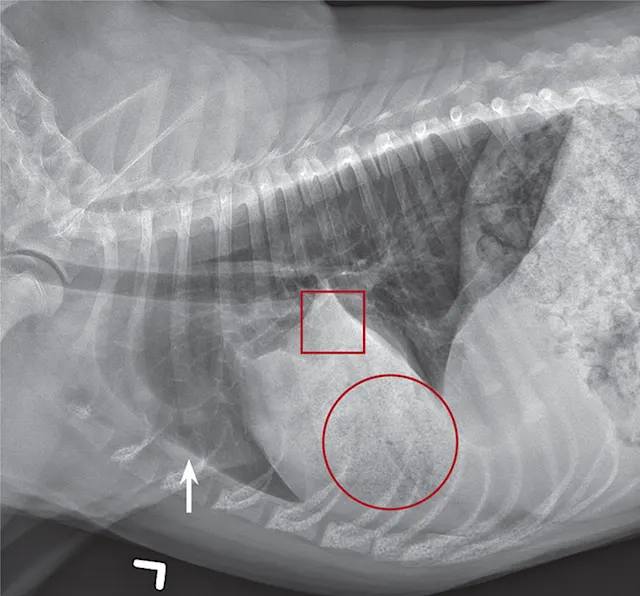

Computed tomography (CT), thoracic ultrasound, and bronchoscopy may be helpful when thoracic radiographs are not diagnostic. CT images (Figure 4) show abruptly ending lobar bronchus of the affected lobe and noncontrast enhancing lung lobe enlargement in addition to pleural effusion and vesicular emphysema.5,6 The torsed lung appears rounded, hypoechoic, and surrounded by pleural effusion on ultrasonography.5 Definitive diagnosis is made by direct inspection at surgery or necropsy.

Figure 2

Ventrodorsal thoracic radiograph of a dog with right middle LLT. There is a vesicular gas pattern and alveolar pattern throughout the right middle lung lobe (circle), and the right middle lobar bronchus abruptly truncates near the hilus (rectangle). There is a moderate volume of pleural effusion evenly distributed within the pleural space, with moderate retraction of all lung lobes away from the thoracic wall (arrows).